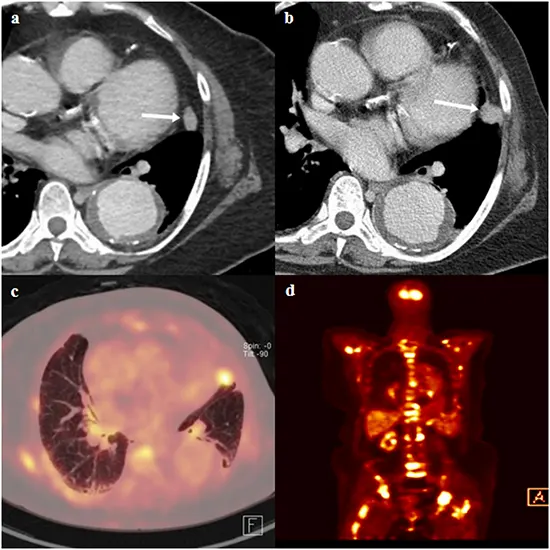

To provide a more complete view of cancer and its spread, CT scans are frequently utilized in conjunction with other Imaging techniques, such as MRI (magnetic resonance imaging) and PET (positron emission tomography) scans.